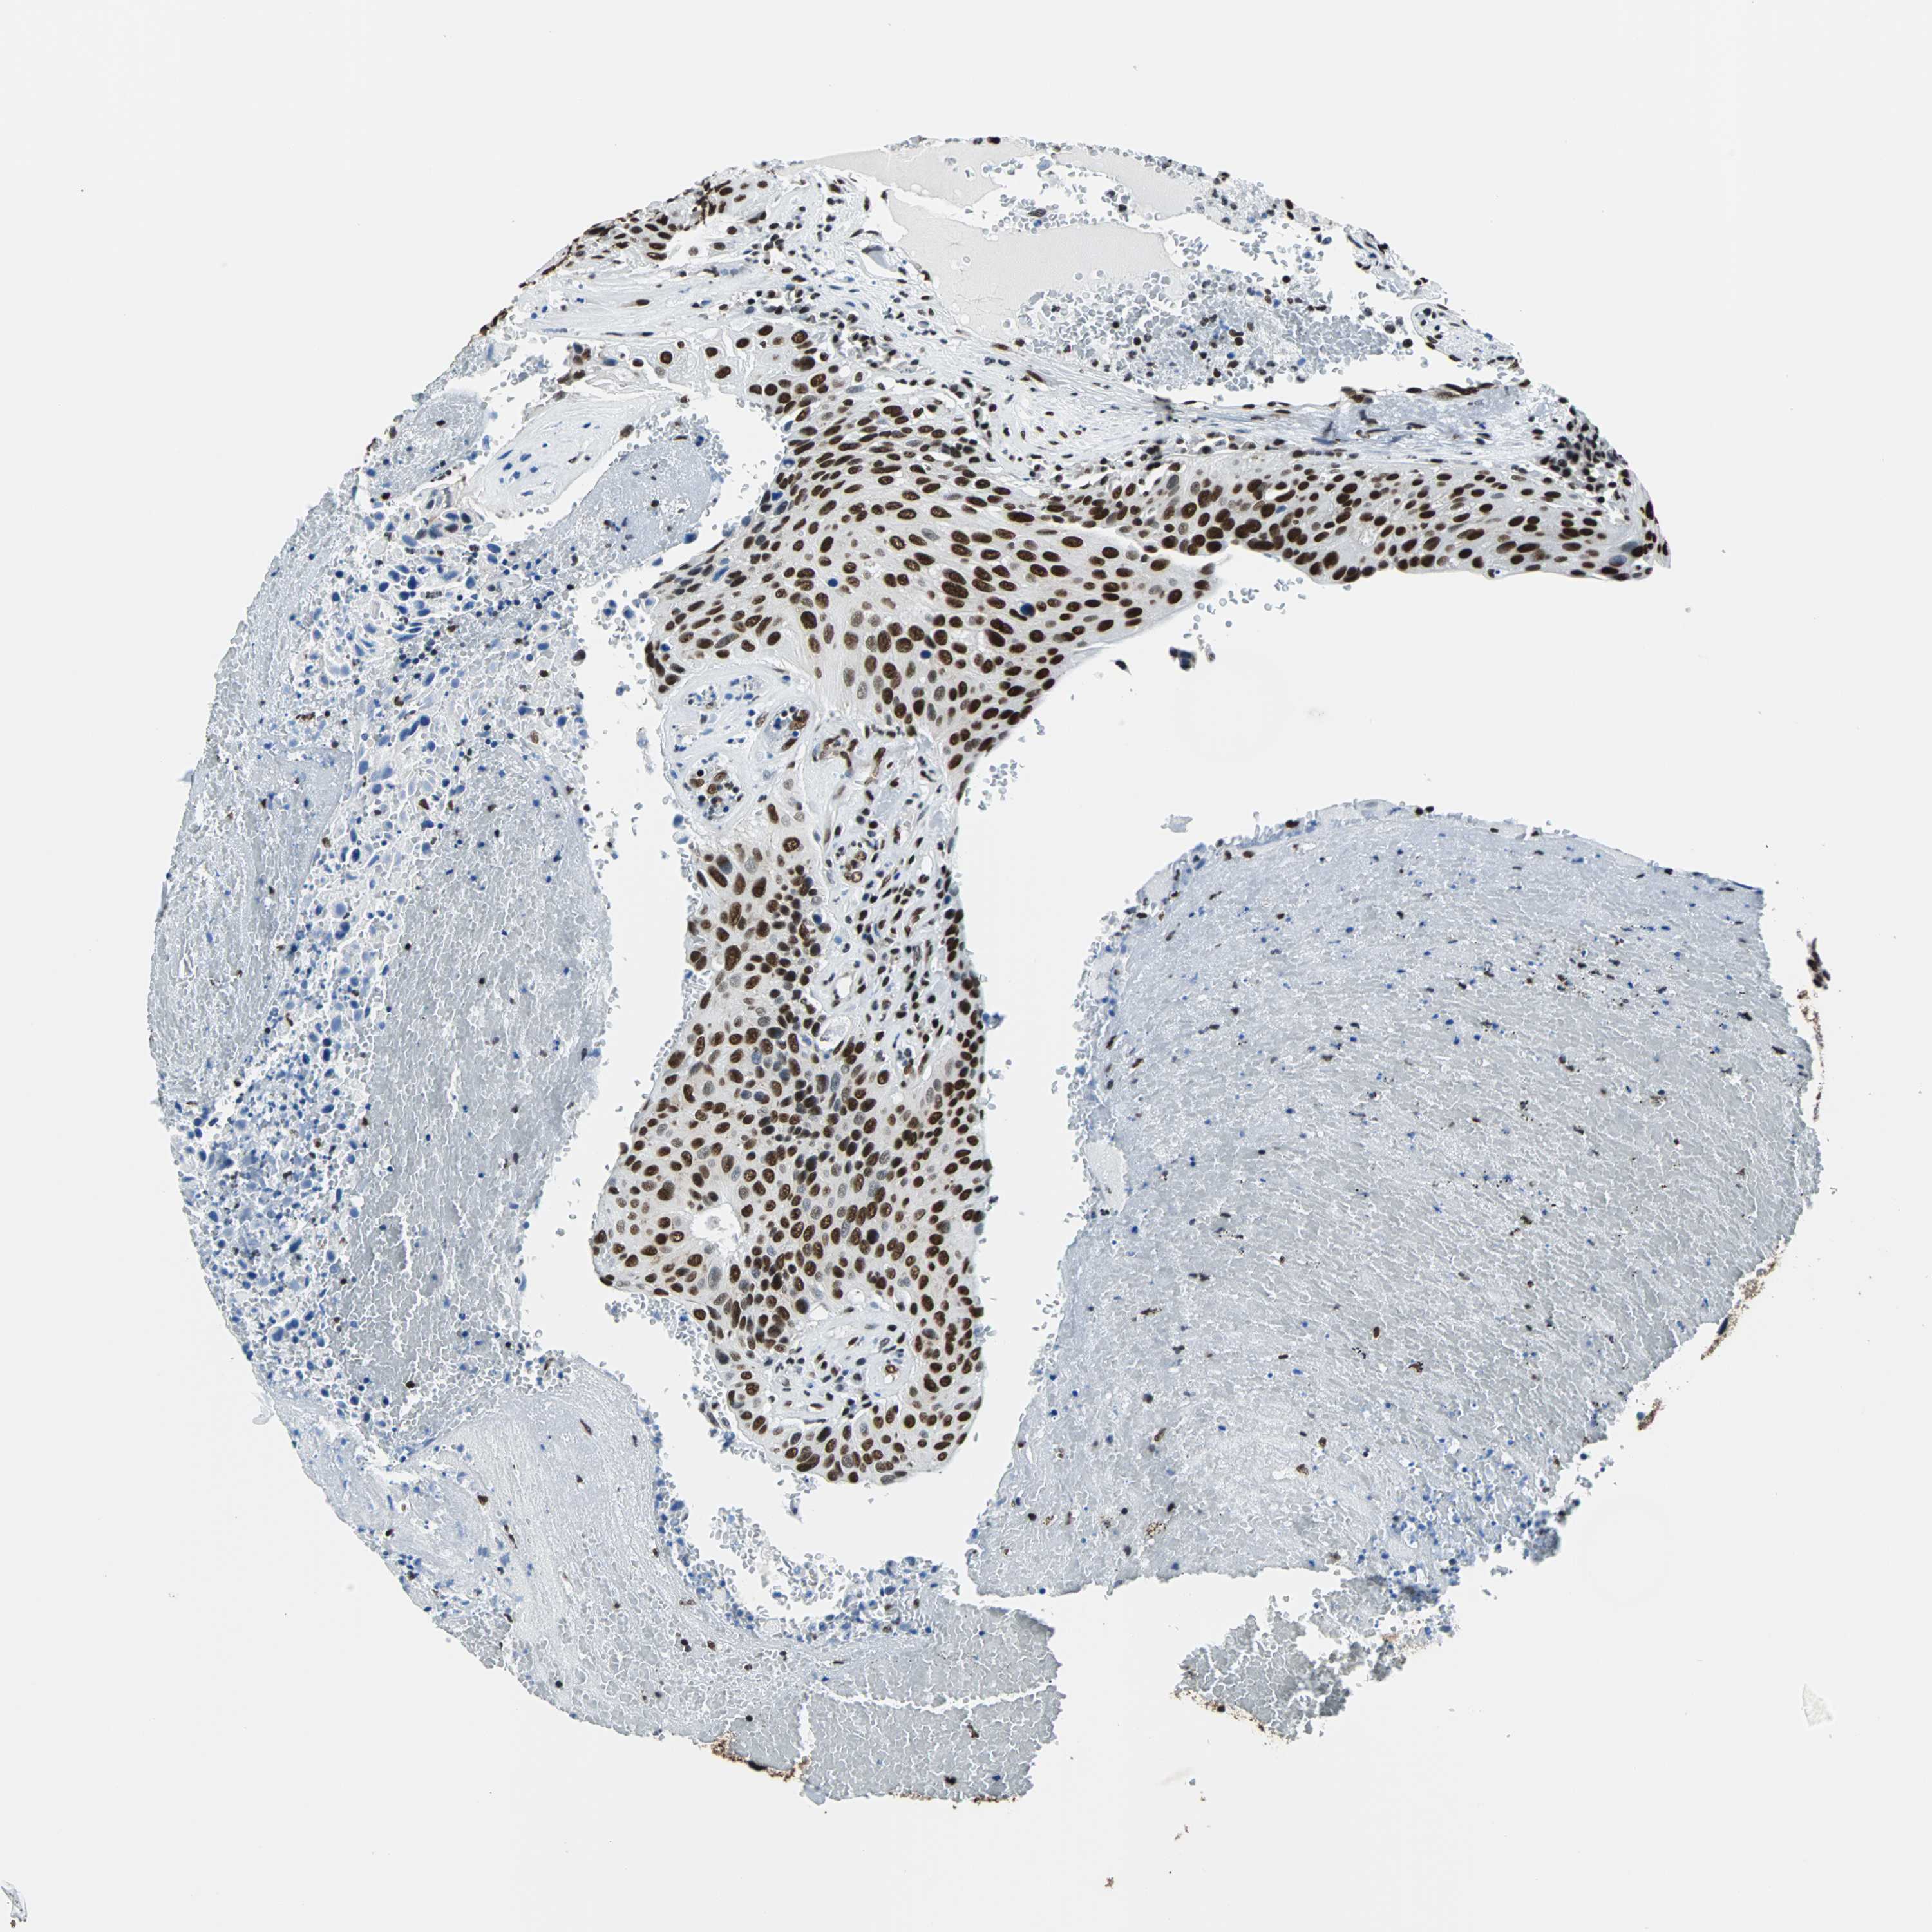

UROTHELIAL CANCER - Protein expressioni

A mouse-over function shows sample information and annotation data. Click on an image to view it in a full screen mode. Samples can be filtered based on level of antibody staining by selecting one or several of the following categories: high, medium, low and not detected. The assay and annotation is described here.

Note that samples used for immunohistochemistry by the Human Protein Atlas do not correspond to samples in the TCGA dataset.

Antibody stainingi

Antibody staining in the annotated cell types in the current human tissue is reported as not detected, low, medium, or high, based on conventional immunohistochemistry profiling in selected tissues. This score is based on the combination of the staining intensity and fraction of stained cells.

Each image is clickable and will lead to virtual microscopy that enables deeper exploration of all samples and also displays staining intensity scores, fraction scores and subcellular localization as well as patient and tissue information for each sample.

Antibody HPA006149

Staining

High

Medium

Low

Not detected

Intensity

Strong

Moderate

Weak

Negative

Quantity

>75%

75%-25%

<25%

None

Location

Nuclear

Cytoplasmic/membranous

Cytoplasmic/membranous,nuclear

Urothelial carcinoma, High grade

Urothelial carcinoma, Low grade